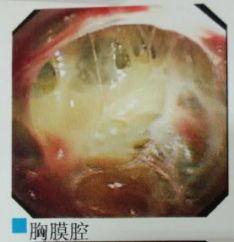

蜘蛛网胸水(包裹性胸腔积液),在胸腔镜下是什么鬼样子的呢?

一大包胸水,看着是不是很好抽?Ease,轻松搞定!

且看胸腔镜:

胸腔里面这么多分隔,你能保证你的针在哪个小分隔里面?除非你有孙悟空的火眼金睛!

在胸腔镜下,是“蜘蛛网+蜂窝状”般的变态存在。

你说说,这种情况怎么愉快的抽胸水?